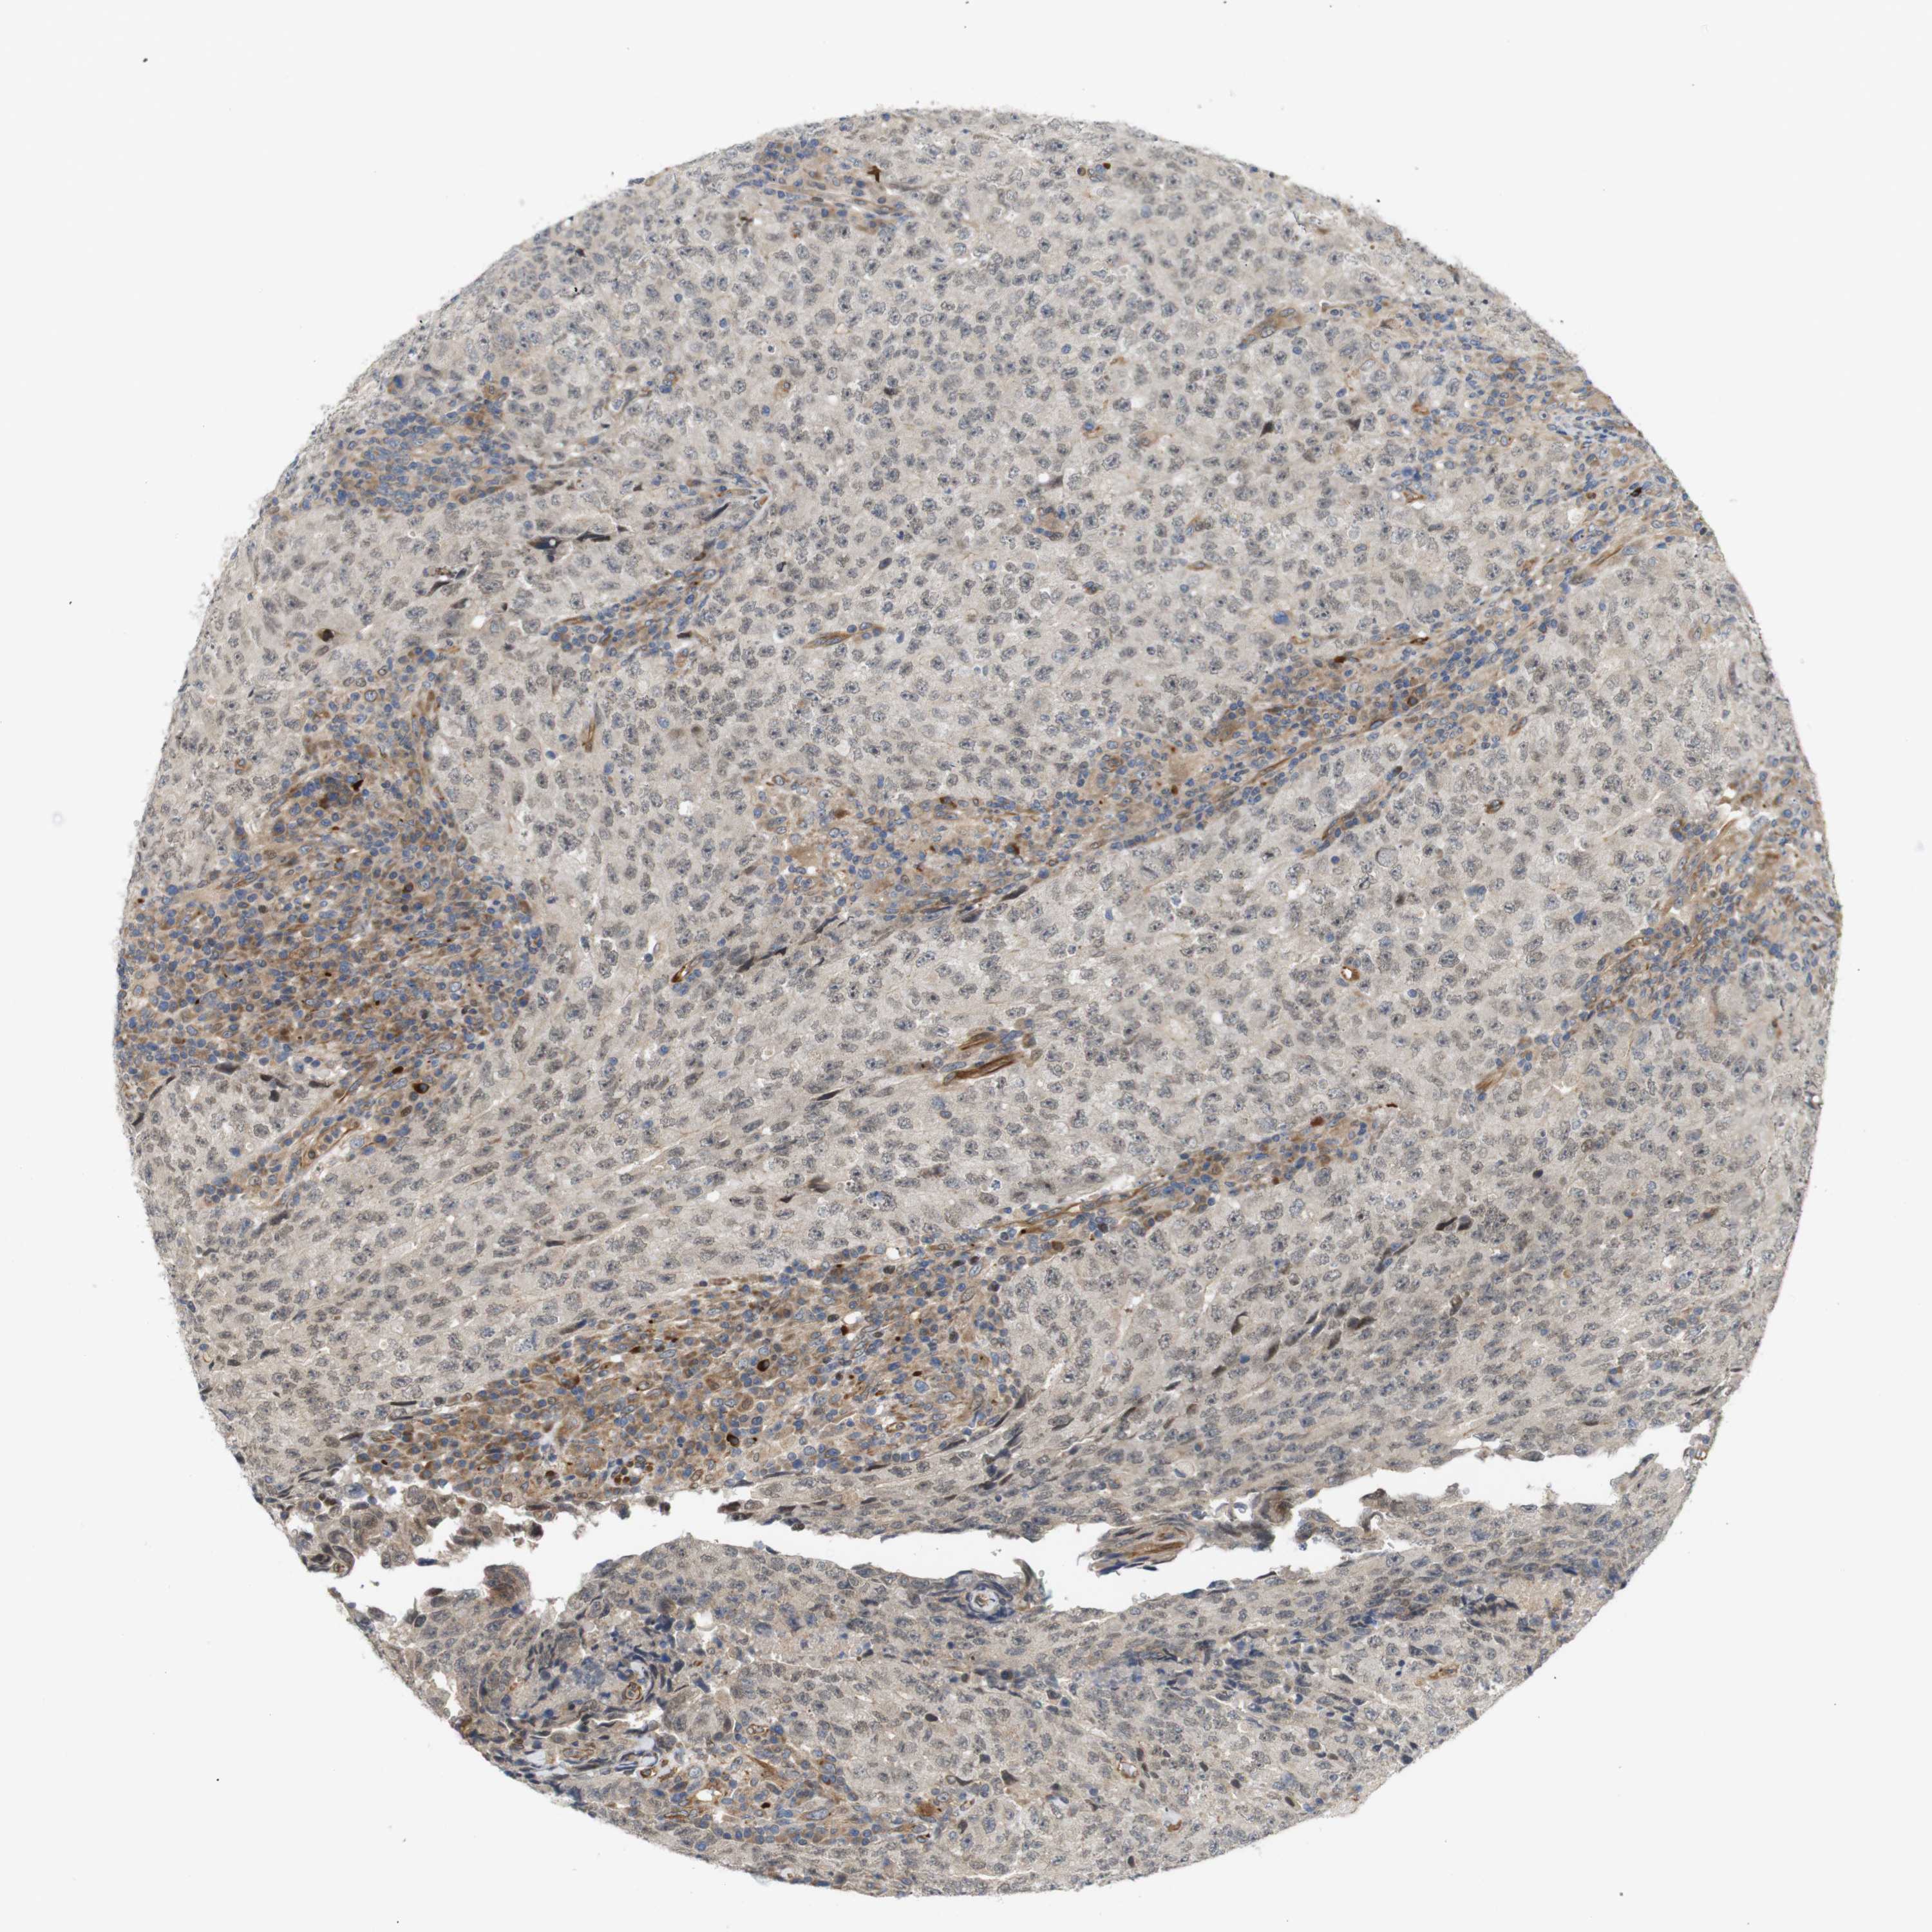

TESTIS CANCER - Protein expressioni

A mouse-over function shows sample information and annotation data. Click on an image to view it in a full screen mode. Samples can be filtered based on level of antibody staining by selecting one or several of the following categories: high, medium, low and not detected. The assay and annotation is described here.

Note that samples used for immunohistochemistry by the Human Protein Atlas do not correspond to samples in the TCGA dataset.

Antibody stainingi

Antibody staining in the annotated cell types in the current human tissue is reported as not detected, low, medium, or high, based on conventional immunohistochemistry profiling in selected tissues. This score is based on the combination of the staining intensity and fraction of stained cells.

Each image is clickable and will lead to virtual microscopy that enables deeper exploration of all samples and also displays staining intensity scores, fraction scores and subcellular localization as well as patient and tissue information for each sample.

Antibody CAB013514

Staining

High

Medium

Low

Not detected

Intensity

Strong

Moderate

Weak

Negative

Quantity

>75%

75%-25%

<25%

None

Location

Nuclear

Cytoplasmic/membranous

Cytoplasmic/membranous,nuclear

Carcinoma, Embryonal, NOS

Seminoma, NOS